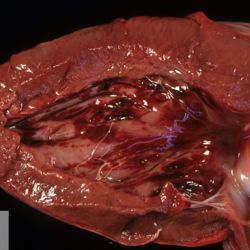

Pàgina anterior de 637 Pàgina següent 3181 total Wildlife Specie: Wildlife Organ: Heart Lesion: Pericarditis Lesion modifier: Pericarditis - Gangrenous Disease: - Files/Expedient: zoo17 Not viewed Wildlife Specie: Wildlife Organ: Heart Lesion: Pericarditis Lesion modifier: Pericarditis - Gangrenous Disease: - Files/Expedient: zoo17 Not viewed Wildlife Specie: Wildlife Organ: Heart Lesion: Pericarditis Lesion modifier: Pericarditis - Gangrenous Disease: - Files/Expedient: zoo17 Not viewed Non-human primate Specie: Non-human primate Organ: Liver Lesion: Cyst Lesion modifier: - Disease: - Not viewed Wildlife Specie: Wildlife Organ: Heart Lesion: Hemorrhage Lesion modifier: - Disease: - Not viewed Pàgina anterior de 637 Pàgina següent Títol Select...Avian (Exotic) (110)Avian (Poultry) (76)Bovine (317)Canine (935)Caprine (47)Equine (257)Feline (326)Ferret (19)General (127)Marine mammal (22)Non-human primate (20)Ovine (328)Porcine (379)Rabbit (61)Reptile (38)Rodent (28)Wildlife (91) Format Select...- (60)Abomasum (37)Adrenal gland (10)Blood (7)Blood vessel (50)Body as a whole (19)Bone (57)Bone marrow (21)Brain (93)Cloaca (1)Diaphragm (2)Ear (5)Esophagus (39)Eye (16)Fetus (12)Gallbladder (23)Gizzard (2)Heart (265)Intestine (356)Joint (32)Kidney (443)Larynx (5)Liver (326)Lung (264)Lymph node (91)Mammary gland (10)Mediastinum (1)Muscle (22)Nasal cavity (22)Nerve (7)Omasum (5)Oral cavity (63)Ovary (14)Oviduct (8)Pancreas (7)Parathyroid (5)Penis (10)Peritoneum (65)Pharynx (9)Pituitary gland (6)Placenta (7)Prostate (8)Proventriculus (3)Reticulum (1)Rumen (28)Sinus (7)Skin (181)Spinal cord (15)Spleen (105)Stomach (125)Teeth (1)Testicle (11)Thoracic cavity (31)Thymus (13)Thyroid gland (5)Tongue (32)Tonsils (11)Trachea (11)Urethra (5)Urinay bladder (61)Uterus (27)Vagina (1)Vulva (1)Yolk sac (1) Cobertura Select...- (152)Abomasitis (26)Abscess (27)Acidosis (1)Adenocarcinoma (20)Adenoma (9)Aerosacculitis (6)Agenesis (1)Agnathia (1)Alopecia (7)Amyloidosis (12)Aneurysm (6)Angiectasis (1)Anthracosis (1)Arteritis (11)Arthritis (15)Arthrogryposis (6)Artifact (4)Ascites (13)Atelectasis (8)Atherosclerosis (5)Atresia (1)Atrial septal defect (2)Atrophy (10)Autolysis (7)Bronchitis (6)Bronchopneumonia (26)Cachexia (2)Carcinoma (103)Cardiomyopathy (19)Cellulitis (2)Chemodectoma (4)Cholangiohepatitis (4)Cholangitis (19)Cholecystitis (4)Cholestasis (5)Chondrodysplasia (2)Chondrosarcoma (2)Chronic passive congestion (13)Chylothorax (2)Cirrhosis (6)Coelomitis (3)Coenurus cerebralis (4)Colitis (40)Congestion (17)Conjunctivitis (5)Coronitis (3)Cryptorchidism (3)Cyst (25)Cystitis (24)Dermatitis (69)Diaphragmatic hernia (4)Dilation (28)Discospondylitis (1)Disseminated intravascular coagulation (7)Dyschondroplasia (1)Dysplasia (29)Ectopia cordis (1)Ectopic ureter (1)Edema (55)Emphysema (5)Encephalitis (5)Endocardiosis (14)Endocarditis (26)Endometritis (5)Enteritis (118)Enterolith (6)Epulis (3)Esophagitis (14)Fasciitis (1)Fibrosis (7)Fibrous osteodystrophy (8)Fistula (1)Folliculitis (3)Fracture (2)Gastritis (34)Gingivitis (5)Glioma (8)Glomerulonephritis (21)Glossitis (25)Glycogenosis (1)Gout (8)Granuloma (2)Granulosa cell tumor (4)Hemangioma (9)Hemangiosarcoma (46)Hematoma (8)Hemoglobinuria (2)Hemopericardium (12)Hemoperitoneum (2)Hemorrhage (100)Hemosiderosis (7)Hemothorax (2)Hepatitis (78)Hernia (11)Histiocytosis (3)Hydatid cyst (11)Hydrocephalus (9)Hydrometra (1)Hydronephrosis (22)Hydropericardium (6)Hydrothorax (3)Hydroureter (5)Hyperkeratosis (8)Hyperostosis (4)Hyperplasia (37)Hypertrophy (9)Hypopigmentation (1)Hypoplasia (7)Hypopyon (1)Impaction (6)Infarction (63)Insulinoma (6)Intussusception (5)Jaundice (17)Laminitis (2)Laryngitis (2)Leiomyoma (5)Leukemia (13)Lipidosis (36)Lipoma (7)Lymphadenitis (45)Lymphadenopathy (7)Lymphangiectasia (6)Lymphangitis (5)Lymphoma (221)Malacia (11)Malignant melanoma (15)Mast cell tumor (11)Mastitis (8)Megaesophagus (2)Melanosis (3)Melena (4)Meningioma (6)Meningitis (6)Meningocele (2)Meningoencephalitis (5)Mesothelioma (5)Methemoglobinemia (2)Mineralization (10)Mucocele (5)Mucometra (1)Multilobular bone tumor (1)Mummification (3)Myelofibrosis (1)Myocarditis (4)Myositis (5)Necrosis (81)Nephritis (113)Nephroblastoma (6)Nephrosclerosis (1)Nephrosis (14)Neuritis (1)Obstruction (13)Omasitis (4)Omphalitis (1)Omphalophlebitis (7)Orchitis (4)Osteoarthrosis (5)Osteomyelitis (9)Otitis (2)Palatoschisis (3)Pancreatitis (3)Panniculitis (3)Papilloma (7)Parakeratosis (14)Patent ductus arteriosus (6)Peliosis hepatis (1)Perforation (17)Pericarditis (35)Peritonitis (39)Persistent right aortic arch (1)Pharyngitis (2)Pheochromocytoma (2)Phlebitis (2)Placentitis (6)Pleuritis (21)Pleuropneumonia (24)Pneumonia (109)Pneumothorax (3)Polycystosis (14)Polyp (5)Polyserositis (6)Posthitis (1)Proctitis (4)Prolapse (3)Prostatitis (3)Proventriculitis (1)Pyelonephritis (24)Pyometra (6)Pyothorax (4)Rhinitis (11)Rumenitis (6)Rupture (24)Salpingitis (3)Sarcoma (57)Sclerosis (1)Scoliosis (2)Seminoma (2)Sequestrum (2)Serous atrophy (14)Sinusitis (7)Splenitis (14)Splenomegaly (9)Spondylitis (6)Spondylosis (1)Stenosis (9)Stomatitis (32)Tenosynovitis (2)Teratoma (3)Thricobezoar (2)Thrombosis (16)Tonsilitis (4)Torsion (13)Tracheitis (4)Tympany (7)Typhlitis (8)Typhlocolitis (4)Ulcer (43)Urethritis (1)Urolithiasis (36)Uroperitoneum (1)Uveitis (1)Vasculitis (15)Ventricular septal defect (3)Volvulus (11) Matèria Select... - (14)- (1653)- (152)Abomasitis - Catarrhal (2)Abomasitis - Catarrhal-hemorrhagic (1)Abomasitis - Chronic (1)Abomasitis - Fibrinous-necrotizing (2)Abomasitis - Hyperplasic (5)Abomasitis - Hyperplasic - Chronic (1)Abomasitis - Necrotic (1)Abomasitis - Necrotizing (2)Abomasitis - Ulcerative (5)Adenocarcinoma (9)Aerosacculitis - Granulomatous (1)Amyloidosis - Chronic (1)Arteritis - Necrotic (2)Arteritis - Necrotizing (1)Arthritis - Chronic (4)Arthritis - Fibrinous-purulent (3)Arthritis - Serous (4)Arthritis - Subacute (1)Ascites - Serous (1)Atrophy - Serous (1)Bronchitis - Catarrhal (3)Bronchitis - Suppurative (1)Bronchopneumonia - Catarrhal-purulent (17)Bronchopneumonia - Fibrinous (1)Bronchopneumonia - Granulomatous (1)Bronchopneumonia - Purulent (1)Bronchopneumonia - Suppurative (5)Carcinoma - Adenocarcinoma (33)Carcinoma - Adenocarcinoma - Hepatocellular (2)Carcinoma - Adenocarcinoma - Mucinous (1)Carcinoma - Basosquamous (1)Carcinoma - Cholangiocellular (3)Carcinoma - Hepatocellular (4)Carcinoma - Metastatic (3)Carcinoma - Squamous cell carcinoma (13)Carcinoma - Transitional cell (2)Cardiomyopathy - Dilated (13)Cardiomyopathy - Hypertrophic (6)Cellulitis - Necrotizing (1)Cholangitis - Chronic (8)Cholangitis - Hyperplasic (3)Cholecystitis - Fibrinous-necrotizing (1)Coelomitis - Fibrinous (1)Coelomitis - Granulomatous (1)Colitis - Catarrhal (3)Colitis - Catarrhal-hemorrhagic (1)Colitis - Fibrinous (1)Colitis - Fibrinous-necrotizing (1)Colitis - Fibrinous-necrotizing (Diphtheritic) (6)Colitis - Granulomatous (2)Colitis - Hemorrhagic (4)Colitis - Hemorrhagic-necrotizing (3)Colitis - Necrotizing (2)Colitis - Ulcerative (6)Congestion - Chronic (2)Conjunctivitis - Hyperplasic (1)Conjunctivitis - Purulent (3)Coronitis - Ulcerative (1)Cystitis - Chronic (3)Cystitis - Fibrinous (1)Cystitis - Fibrinous-necrotizing (1)Cystitis - Follicular (1)Cystitis - Hemorrhagic (6)Cystitis - Hemorrhagic-ulcerative (1)Cystitis - Necrotizing (9)Cystitis - Perforated (1)Dermatitis - Granulomatous (14)Dermatitis - Hyperkeratotic (10)Dermatitis - Hyperplasic (proliferative) (1)Dermatitis - Hyperplastic (10)Dermatitis - Necrotizing (4)Dermatitis - Pustular (4)Dermatitis - Ulcerative (2)Dilation - Chronic (1)Discospondylitis - Necrotizing (1)Dysplasia - Follicular (5)Edema - Interstitial (6)Emphysema - Interstitial (1)Encephalitis - Granulomatous (1)Encephalitis - Nonsuppurative (1)Endocardiosis - Mitral (7)Endocardiosis - Mitral - Chronic (5)Endocarditis - Valvular (6)Endocarditis - Valvular - Mitral (7)Endocarditis - Valvular - Pulmonic (1)Endocarditis - Valvular - Subacute (1)Endocarditis - Valvular - Subaortic (5)Endocarditis - Valvular - Tricuspid (4)Endometritis - Purulent (3)Endometritis - Purulent-hemorrhagic (2)Enteritis - Catarrhal (23)Enteritis - Catarrhal - Acute (1)Enteritis - Catarrhal-hemorrhagic (5)Enteritis - Catarrhal-hemorrhagic - Acute (2)Enteritis - Fibrinous (16)Enteritis - Fibrinous - Acute (3)Enteritis - Fibrinous-necrotizing (7)Enteritis - Granulomatous (14)Enteritis - Granulomatous - Chronic (1)Enteritis - Granulomatous - Multifocal (1)Enteritis - Hemorrhagic (17)Enteritis - Hemorrhagic - Acute (1)Enteritis - Hemorrhagic-necrotizing (1)Enteritis - Hyperplasic (proliferative) (4)Enteritis - Necrotizing (4)Enteritis - Necrotizing - Acute (1)Enteritis - Necrotizing - Hemorrhagic (1)Enteritis - Necrotizing-ulcerative (2)Enteritis - Ulcerative (1)Enteritis - Ulcerative-hemorrhagic (1)Esophagitis - Erosive-ulcerative (6)Esophagitis - Necrotizing (4)Esophagitis - Ulcerative (1)Esophagitis - Ulcerative-necrotizing (1)Fasciitis - Fibrinous-purulent (1)Folliculitis - Purulent (2)Gastritis - Catarrhal (2)Gastritis - Chronic (1)Gastritis - Follicular (1)Gastritis - Hemorrhagic (2)Gastritis - Hemorrhagic-necrotizing (1)Gastritis - Hypertrophic (2)Gastritis - Inclusion bodies (1)Gastritis - Mineralization (1)Gastritis - Mycotic (1)Gastritis - Necrotizing (2)Gastritis - Ulcerative (6)Gastritis - Uremic (3)Gingivitis - Erosive (2)Gingivitis - Hyperplasic (proliferative) (1)Gingivitis - Necrotizing (1)Glomerulonephritis - Chronic (7)Glomerulonephritis - Membranoproliferative (3)Glomerulonephritis - Membranoproliferative - Chronic (1)Glomerulonephritis - Membranous (3)Glomerulonephritis - Membranous - Chronic (1)Glomerulonephritis - Proliferative (2)Glomerulonephritis - Subacute (1)Glossitis - Erosive (2)Glossitis - Granulomatous (6)Glossitis - Hyperplasic (1)Glossitis - Hyperplasic (proliferative) (2)Glossitis - Hyperplastic (1)Glossitis - Necrotizing (2)Glossitis - Necrotizing - Focal (1)Glossitis - Ulcerative (6)Glossitis - Ulcerative - Multifocal (1)Glossitis - Ulcerative - Subacute (1)Glycogenosis (1)Granuloma - Eosinophilic (1)Hemangiosarcoma - Metastatic (2)Hemorrhage - Acute (1)Hemorrhage - Subcapsular (3)Hepatitis - Abscess (9)Hepatitis - Acute (3)Hepatitis - Chronic (4)Hepatitis - Chronic interstitial (6)Hepatitis - Granulomatous (7)Hepatitis - Interstitial - Multifocal (1)Hepatitis - Interstitial - Subacute (1)Hepatitis - Necrotizing (17)Hepatitis - Necrotizing - Acute (2)Hepatitis - Necrotizing - Hemorrhagic (1)Hepatitis - Necrotizing - Subacute (1)Hepatitis - Pyogranulomatous (7)Hepatitis - Subacute (4)Hydronephrosis - Chronic (1)Hydropericardium - Chronic (1)Hyperplasia - Erythroid (1)Hyperplasia - Lymphoid (3)Hyperplasia - Myeloid (1)Hyperplasia - Nodular (8)Hypertrophy - Concentric (2)Hypertrophy - Eccentric (3)Infarction - Acute (17)Infarction - Acute - Multifocal (2)Infarction - Chronic (5)Infarction - Chronic - Multifocal (1)Infarction - Subacute (18)Infarction - Subacute - Focal (2)Laminitis - Chronic (2)Laryngitis - Necrotic (1)Laryngitis - Necrotizing (1)Leukemia - Lymphoid leukemia (2)Leukemia - Non-lymphoid leukemia (6)Lipidosis - Multifocal (1)Lipidosis - Panlobular (1)Lipidosis - Panlobular - Generalized (2)Lymphadenitis - Granulomatous (24)Lymphadenitis - Granulomatous - Chronic (3)Lymphadenitis - Hemorrhagic (1)Lymphadenitis - Necrotizing (5)Lymphadenitis - Necrotizing (caseous) (11)Lymphangitis - Granulomatous (1)Lymphangitis - Purulent (1)Lymphangitis - Ulcerative (1)Lymphoma - Alimentary lymphoma (7)Lymphoma - Cutaneous lymphoma (6)Lymphoma - Lymphosarcoma (2)Lymphoma - Mediastinal lymphoma (1)Lymphoma - Multicentric lymphoma (29)Malignant melanoma - Malignant (1)Malignant melanoma - Metastatic (1)Mast cell tumor - Metastatic (1)Mastitis - Fibrinous-purulent (2)Mastitis - Necrotic (1)Mastitis - Purulent (3)Mastitis - Suppurative (1)Meningitis - Fibrinous-purulent (2)Meningitis - Purulent (4)Meningoencephalitis - Necrotizing (3)Meningoencephalitis - Nonsuppurative (2)Mineralization - Metastatic (4)Myocarditis - Fibrous - Chronic (1)Myocarditis - Granulomatous (1)Myositis - Purulent (2)Necrosis - Acute (1)Necrosis - Cortical (5)Necrosis - Follicular (1)Necrosis - Papillary (8)Necrosis - Papillary - Acute (3)Necrosis - Subacute (3)Necrosis - Tubular (6)Nephritis - Embolic (2)Nephritis - Embolic suppurative (7)Nephritis - Granulomatous (27)Nephritis - Granulomatous - Chronic (1)Nephritis - Granulomatous - Multifocal (1)Nephritis - Interstitial (6)Nephritis - Interstitial - Acute (4)Nephritis - Interstitial - Chronic (41)Nephritis - Interstitial - Subacute (12)Nephritis - Purulent (7)Nephritis - Purulent - Acute (2)Nephritis - Purulent - Multifocal (3)Nephrosis - Cholemic (3)Nephrosis - Hemoglobinuric (10)Omasitis - Fibrinous-necrotizing (1)Omasitis - Hyperkeratotic (1)Omasitis - Necrotizing (2)Omphalophlebitis - Fibrinous-purulent (2)Omphalophlebitis - Purulent (3)Orchitis - Necrotizing (1)Osteomyelitis - Necrotizing (7)Osteomyelitis - Purulent (2)Otitis - Necrotizing (1)Otitis - Proliferative (1)Pancreatitis - Acute (1)Pancreatitis - Chronic (1)Pancreatitis - Granulomatous (1)Panniculitis - Fibrinous-purulent (1)Panniculitis - Necrotic (1)Panniculitis - Parasitic (1)Perforation - Acute (2)Pericarditis - Fibrinous (19)Pericarditis - Fibrinous - Subacute (1)Pericarditis - Fibrinous-necrotizing (1)Pericarditis - Fibrinous-purulent (3)Pericarditis - Fibrous (1)Pericarditis - Fibrous - Chronic (1)Pericarditis - Gangrenous (6)Pericarditis - Granulomatous (1)Pericarditis - Granulomatous - Chronic (2)Peritonitis - Acute (1)Peritonitis - Fibrinous (11)Peritonitis - Fibrinous - Subacute (1)Peritonitis - Fibrinous-purulent (5)Peritonitis - Fibrous (3)Peritonitis - Granulomatous (6)Peritonitis - Purulent (1)Peritonitis - Purulent-hemorrhagic (1)Peritonitis - Pyogranulomatous (3)Pharyngitis - Fibrinous-necrotizing (1)Pharyngitis - Ulcerative (1)Pheochromocytoma - Metastatic (1)Phlebitis - Purulent (1)Placentitis - Fibrinous-necrotizing (1)Placentitis - Necrotic (1)Placentitis - Necrotizing (1)Pleuritis - Chronic (1)Pleuritis - Fibrinous (3)Pleuritis - Fibrinous-purulent (2)Pleuritis - Fibrous (2)Pleuritis - Granulomatous (3)Pleuritis - Hyperplastic (2)Pleuritis - Purulent (2)Pleuritis - Pyogranulomatous (1)Pleuropneumonia - Fibrinous (13)Pleuropneumonia - Fibrinous-necrotizing (5)Pleuropneumonia - Granulomatous (2)Pleuropneumonia - Hemorrhagic-necrotizing (4)Pneumonia - Aspiration (11)Pneumonia - Bronchointerstitial (4)Pneumonia - Bronchointerstitial - Subacute (1)Pneumonia - Embolic (5)Pneumonia - Granulomatous (37)Pneumonia - Granulomatous - Multifocal (4)Pneumonia - Hemorrhagic-necrotizing (2)Pneumonia - Interstitial (7)Pneumonia - Interstitial - Acute (8)Pneumonia - Interstitial - Chronic (6)Pneumonia - Interstitial - Subacute (15)Pneumonia - Necrotizing (2)Pneumonia - Pyogranulomatous (2)Pneumonia - Verminous (5)Polyserositis - Fibrinous (6)Polyserositis - Fibrous (1)Proctitis - Fibrinous-necrotizing (1)Proctitis - Parasitic (2)Prostatitis - Purulent (1)Pyelonephritis - Acute (2)Pyelonephritis - Chronic (3)Rhinitis - Catarrhal (2)Rhinitis - Fibrinous (1)Rhinitis - Granulomatous (4)Rhinitis - Purulent (3)Rumenitis - Acute (1)Rumenitis - Erosive (1)Rumenitis - Necrotizing (1)Rupture - Acute (3)Sarcoma - Fibrosarcoma (12)Sarcoma - Hemangiosarcoma (11)Sarcoma - Histiocytic (7)Sarcoma - Metastatic (1)Sarcoma - Multilobular tumor of bone (1)Sequestrum - Chronic (2)Sinusitis - Suppurative (1)Splenitis - Granulomatous (8)Splenitis - Granulomatous - Chronic (1)Splenitis - Necrotizing (3)Splenitis - Necrotizing (caseous) (2)Spondylitis - Necrotizing (2)Stenosis - Intestinal (1)Stenosis - Valvular - Subaortic (4)Stomatitis - Erosive (12)Stomatitis - Erosive-ulcerative (3)Stomatitis - Fibrinous-necrotizing (1)Stomatitis - Fibrinous-necrotizing (Diphtheritic) (1)Stomatitis - Granulomatous (1)Stomatitis - Hyperplasic (1)Stomatitis - Hyperplasic (proliferative) (1)Stomatitis - Necrotizing (2)Stomatitis - Ulcerative (5)Stomatitis - Ulcerative - Multifocal (1)Stomatitis - Ulcerative-necrotizing (1)Tonsilitis - Necrotizing (4)Torsion - Acute passive hyperemia (5)Tracheitis - Catarrhal (3)Tracheitis - Fibrinous (1)Tracheitis - Granulomatous (1)Typhlitis - Catarrhal (1)Typhlitis - Fibrinous-necrotizing (2)Typhlitis - Hemorrhagic (2)Typhlitis - Ulcerative-hemorrhagic (1)Typhlocolitis - Fibrinous-necrotizing (2)Typhlocolitis - Proliferative (1)Ulcer - Chronic (6)Ulcer - Multifocal (2)Ulcer - Mycotic (1)Ulcer - Perforated (6)Urethritis - Hemorrhagic (1)Urolithiasis - Chronic (2)Uveitis - Granulomatous (1)Vasculitis - Granulomatous (1)Vasculitis - Necrotizing (1) Editor Select...- (1970)Acidosis (2)Actinobacillosis (Pleuropneumonia) (11)Aelurostrongylosis (2)African horse sickness (13)African swine fever (14)Alopecia X (1)Anaplasmosis (4)Anthrax (2)Aortic thromboembolism (feline) (7)Ascariasis (15)Aspergillosis (18)Atopic dermatitis (1)Atrophic rhinitis (3)Babesiosis (6)Blackhead (1)Bluetongue (11)Border disease (2)Bovine viral diarrhea (21)Brucellosis (2)Candidiasis (5)Canine distemper (14)Caprine arthritis-encephalitis (2)Capture myopathy (1)Cardiac insufficiency (17)Caseous lymphadenitis (7)Chlamydiosis (2)Classical swine fever (19)Clostridiosis (19)Coccidiosis (9)Coenurosis (4)Colibacillosis (21)Contagious ecthyma (7)Copper toxicosis (11)Cowdriosis (Heartwater) (3)Cryptococcosis (3)Cryptosporidiosis (2)Cysticercosis (23)Demodicosis (1)Diabetes (1)Dicrocoeliosis (5)Dictyocaulosis (4)Dirofilariasis (7)Discoid lupus erythematosus (3)Echinococcosis (17)Edema disease (7)Egg drop syndrome (1)Encephalitozoonosis (5)Enterotoxemia (1)Enzootic bovine leukosis (46)Epitheliogenesis imperfecta (3)Equine rhinopneumonitis (2)Equine verminous arteritis (strongylosis) (7)Erysipelas (5)Exudative epidermitis (7)Fasciolasis (11)Feline eosinophilic dermatoses (1)Feline hepatic lipidosis (8)Feline histiocytosis (4)Feline infectious peritonitis (38)Feline leukemia (4)Feline lower urinary tract disease (3)Feline panleukopenia (16)Feline viral rhinotracheitis (1)Flea allergy dermatitis (1)Foot and mouth disease (2)Gasterophilosis (4)Glasser's disease (15)Gousiekte (4)Gout (6)Haemonchosis (9)Hemolytic anemia (4)Hemorrhagic diathesis (1)Hepatic insufficiency (11)Hepatosis dietetica (7)Herpesvirosis (6)Hyperadrenocorticism (7)Hyperparathyroidism (10)Hypertrophic osteopathy (6)Hypervitaminosis D (1)Hypodermosis (1)Inclusion body hepatitis (4)Infectious bovine rhinotracheitis (5)Infectious bronchitis (5)Infectious canine hepatitis (13)Influenza (4)Juvenile nephropathy (8)Lamb dysentery (4)Leishmaniasis (28)Leptospirosis (1)Leukosis (5)Listeriosis (4)Lumpy skin disease (3)Maedi-visna (4)Malignant catarrhal fever (12)Mange (6)Mannheimiosis (5)Marek's disease (7)Metabolic bone disease (2)Mucoid enteropathy (5)Mulberry heart disease (5)Myasis (1)Mycobacteriosis (22)Mycosis fungoides (6)Myxomatosis (3)Necrobacillosis (5)Neonatal isoerythrolysis (6)Nocardiosis (4)Oestrosis (2)Onchocerciasis (1)Osteochondrosis (1)Ostertagiosis (6)Ovine pulmonary adenocarcinoma (5)Oxyuriasis (1)Pacheco's disease (4)Papillomatosis (6)Paratuberculosis (18)Parvovirosis (17)Pasteurellosis (11)Pemphigus foliaceus (1)Periodontal disease (1)Polioencephalomalacia of ruminants (4)Polyarteritis nodosa (3)Polycystic kidney disease (13)Porcine circovirosis (11)Porcine dermatitis and nephropathy syndrome (9)Porcine proliferative enteropathy (4)Porcine reproductive and respiratory syndrome (6)Porcine stress syndrome (1)Pox (13)Pregnancy toxemia (3)Proventricular dilatation disease (2)Pseudotuberculosis (yersiniosis) (2)Psittacine beak and feather disease (PBFD) (5)Pyoderma (4)Q fever (4)Rabbit hemorrhagic disease (2)Renal insufficiency (12)Reticuloendotheliosis (2)Rhodococcosis (1)Rickets (1)Rinderpest (2)Salmonellosis (34)Sarcosporidiosis (2)Schmallenberg (7)Septicemia (23)Spirocercosis (11)Streptococcosis (5)Strongylosis (1)Swine dysentery (5)Systemic coronavirosis (5)Tetralogy of Fallot (5)Theileriosis (13)Thromboembolism (5)Toxoplasmosis (11)Transmissible viral proventriculitis (1)Traumatic reticuloperitonitis (3)Traumatism (16)Tuberculosis (58)Ulcerative lymphangitis (1)Uremic syndrome (20)Viral arthritis (6)White muscle disease (9)Wobbler syndrome (2)Xanthomatosis (1)Zygomycosis (4) Idioma Select...- (1180)Bacterial (501)Degeneration (106)Fungal (46)Hemodynamic (112)Idiopathic (22)Inflammation (58)Malformation (88)Neoplasia (343)Nutritional (41)Parasitic (243)Physical/Chemical (93)Toxic (44)Viral (304) Ítem destacat Canine Puppy. Corneal edema